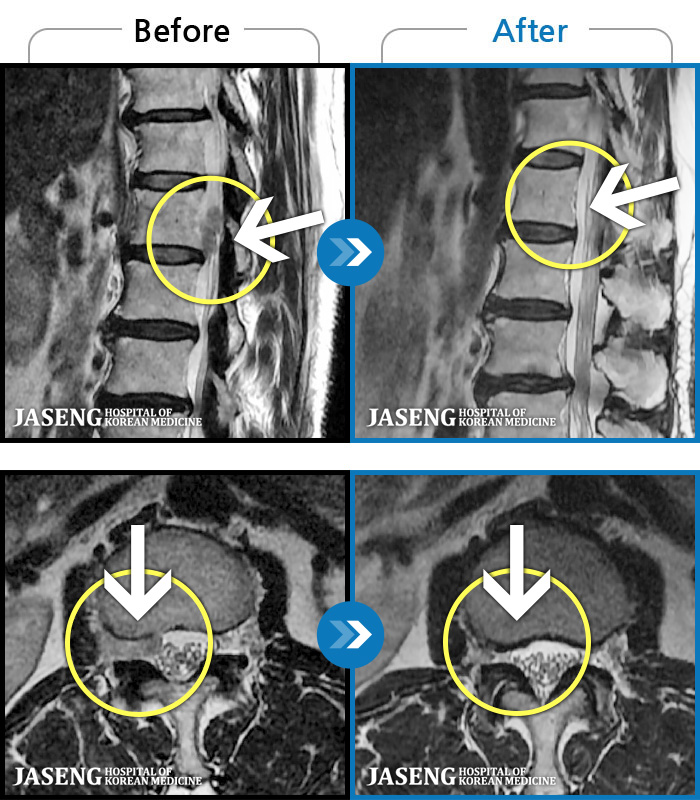

허리디스크

도움받은 사례

해운대 · 김상돈 원장

하지 저림과 통증이 개선되어서 일상생활이 너무 즐겁습니다.

촬영시기

2023.09.18 ~ 2025.01.27

2025.02.05